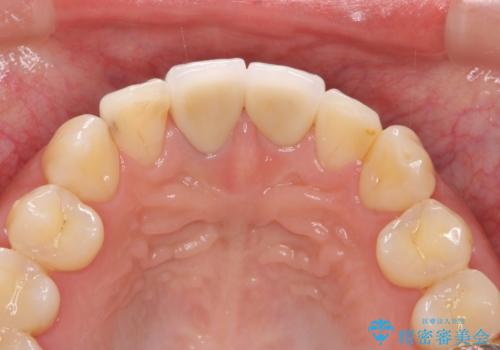

- 32万円(仮歯・ファイバーコア・ジルコニアクラウン×2)費用は治療当時の料金となります

最終的なセラミッククラウンの精度・色調は非常に大事ですが、そこに至るまでの根管内環境の洗浄、ファイバーコアによる緊密な封鎖も長期的な予後に重要であると考えます。